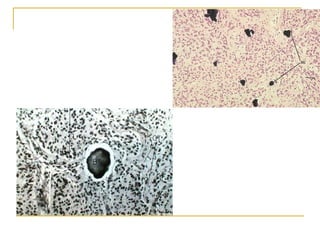

Glândulas paratireóides  2 superiores e 2 inferiores Incluídas na face posterior da cápsula da glândula tireóide

Composta   Células principais  Células oxífilas  Produz  Paratormônio (PTH) Atua nos ossos, rins e intestinos, regulam as concentrações de cálcio sérico Glândulas paratireóides

Glândulas paratireóides Células principais Células funcionais Contém grânulos de paratormônio Células oxífilas Maiores coram-se mais intensamente, em número menor  Função desconhecida - estágios inativos das células principais?

Glândulas paratireóides